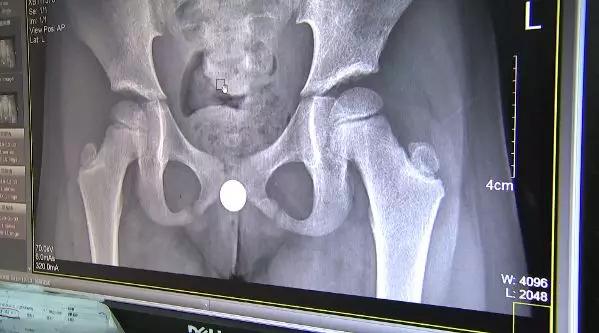

一年后再次就诊,CT结果出来后发现楚楚的阴道内有一个“Y”形的异物,这应该就是“会阴红肿,分泌物增多”的罪魁祸首。